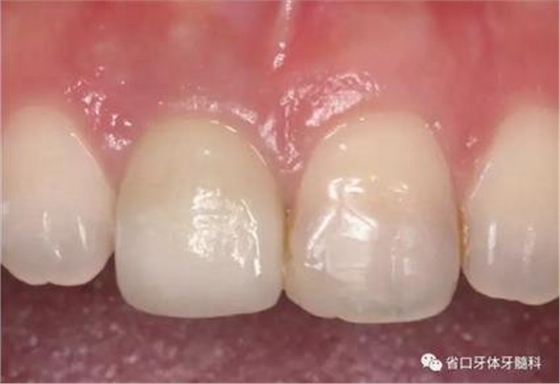

(4)最終修復(fù)與隨訪:經(jīng)過3個月左右的塑形,上頜右側(cè)中切牙臨時修復(fù)固位良好,菌斑控制良好,近遠(yuǎn)中齦乳頭充盈良好,齦緣水平及形態(tài)與 鄰牙相對稱。牙齦塑形穩(wěn)定后,以臨時修復(fù)體制作個性化轉(zhuǎn)移桿并取模轉(zhuǎn)移,并以原廠氧化鋯基臺制備個性化基臺及全瓷冠。正確就位最終基臺,加 力30N·cm。制備粘接代型,去除多余粘接劑,以Unicem粘接固位上頜右側(cè)中切牙全瓷修復(fù)體。固化穩(wěn)定后,再次確定咬合無干擾。最終修復(fù)完成后 隨訪3個月及6個月,上頜右側(cè)中切牙種植修復(fù)固位穩(wěn)定,近遠(yuǎn)中齦乳頭充 盈良好,唇側(cè)齦緣水平穩(wěn)定。

圖34 負(fù)重3個月后

圖35 負(fù)重6個月后復(fù)診

上頜右側(cè)中切牙修復(fù)體固位良好,牙齦乳頭充盈良好,齦緣水平對稱 修復(fù)體與對側(cè)同名牙協(xié)調(diào)一致。外觀笑容美觀協(xié)調(diào)?;颊邼M意。X線檢查示 上頜右側(cè)中切牙種植體周穩(wěn)定骨質(zhì)包繞,唇側(cè)骨板>2mm,相鄰牙槽骨高度穩(wěn)定,基臺及修復(fù)體就位良好。分別根據(jù)Furhauser的PES和Bulser的WES 進(jìn)行美學(xué)評分,總分值為20,美學(xué)效果良好。